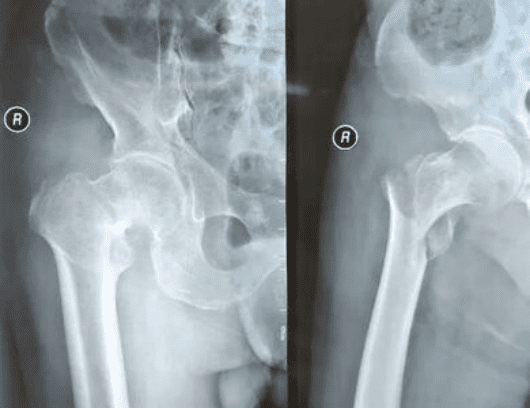

A 100-year-old male patient presented to the hospital with right hip joint pain and limited mobility, symptoms that had persisted for five days following a fall. After admission, the patient was diagnosed with a right intertrochanteric fracture of the femur. Due to the patient’s age, Dr. Cheng fully demonstrated the case, combining the actual situation of the patient with anesthesia in collaboration with related departments, decided to choose the Tri-max nail for minimally invasive closed reduction and internal fixation of fractures for surgical treatment, and formulated a meticulous surgical plan.